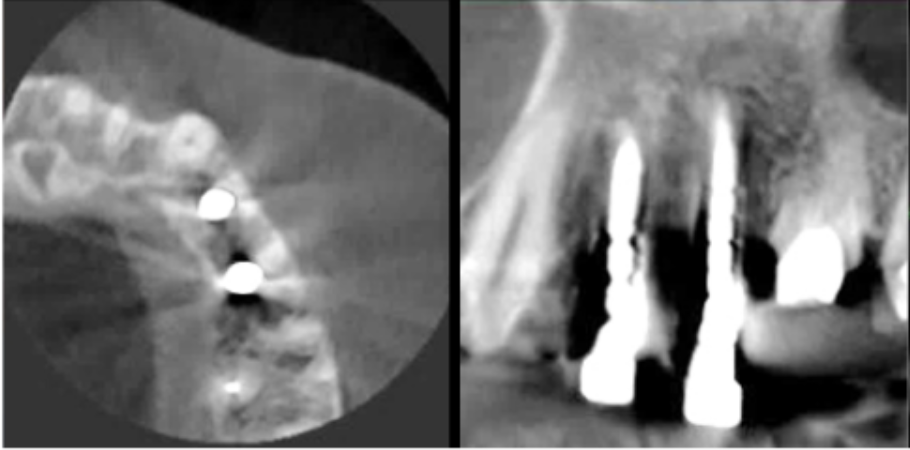

サージカルガイドの作成

インプラント埋入前のCTによる確認